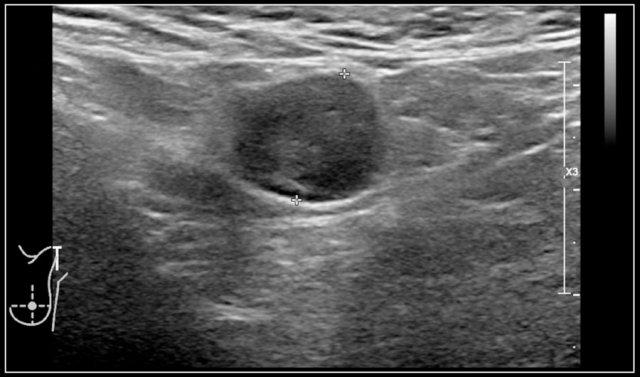

Đây là hình ảnh cắt ngang của một nang ống giáp lưỡi trống âm nằm ngay bên trái đường giữa.